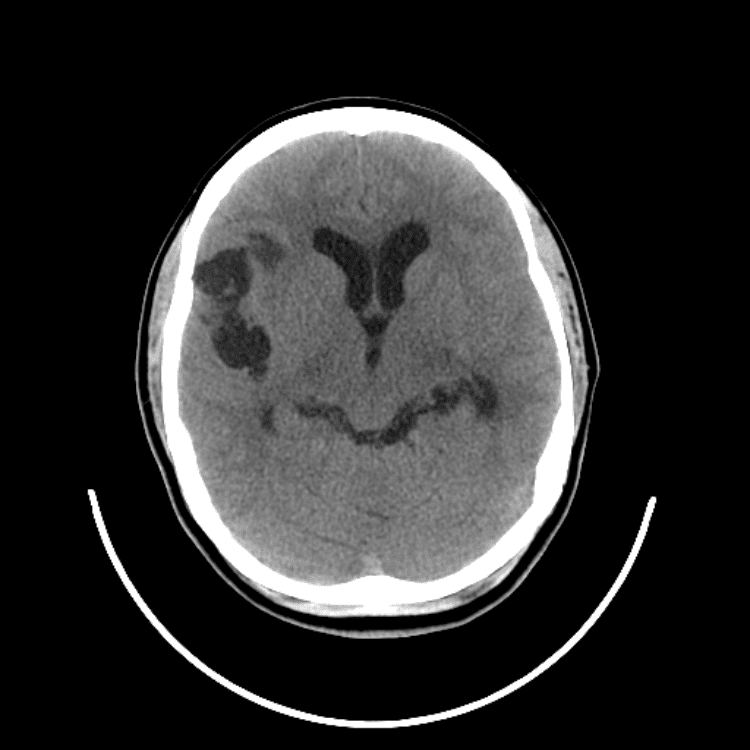

Nontraumatic Brain

Classic